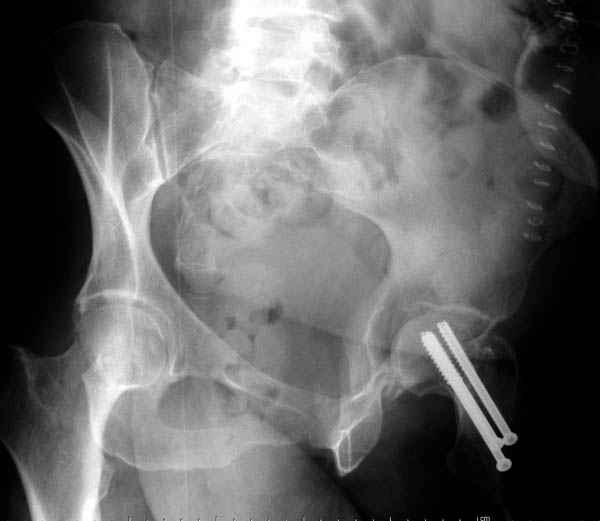

Перелом шейки смогли зафиксировать через пару дней, ацетабулум до сих пор не оперирован, на вытяжении.

Из-за упущенного времени (три недели с момента

поступления) ацетабулум ведем консервативно.

На снимке ацетабулума редко встречающийся очень низкий перелом, наверное, трудно было репозицию через один доступ? Перелом как бы замкнулся в квадрилатеральной поврехности.